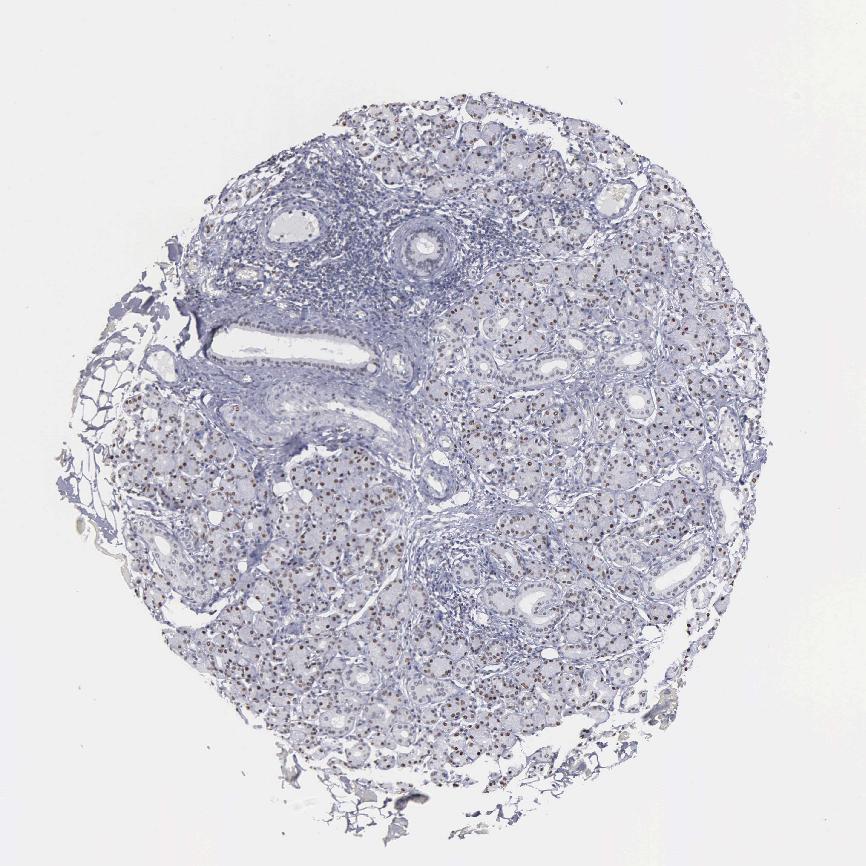

SALIVARY GLAND - Antibody stainingi

Antibody staining in the annotated cell types in the current human tissue is reported as not detected, low, medium, or high, based on conventional immunohistochemistry profiling in selected tissues. This score is based on the combination of the staining intensity and fraction of stained cells.

Each image is clickable and will lead to virtual microscopy that enables deeper exploration of all samples and also displays staining intensity scores, fraction scores and subcellular localization as well as patient and tissue information for each sample.

Antibody CAB000350

Glandular cells High